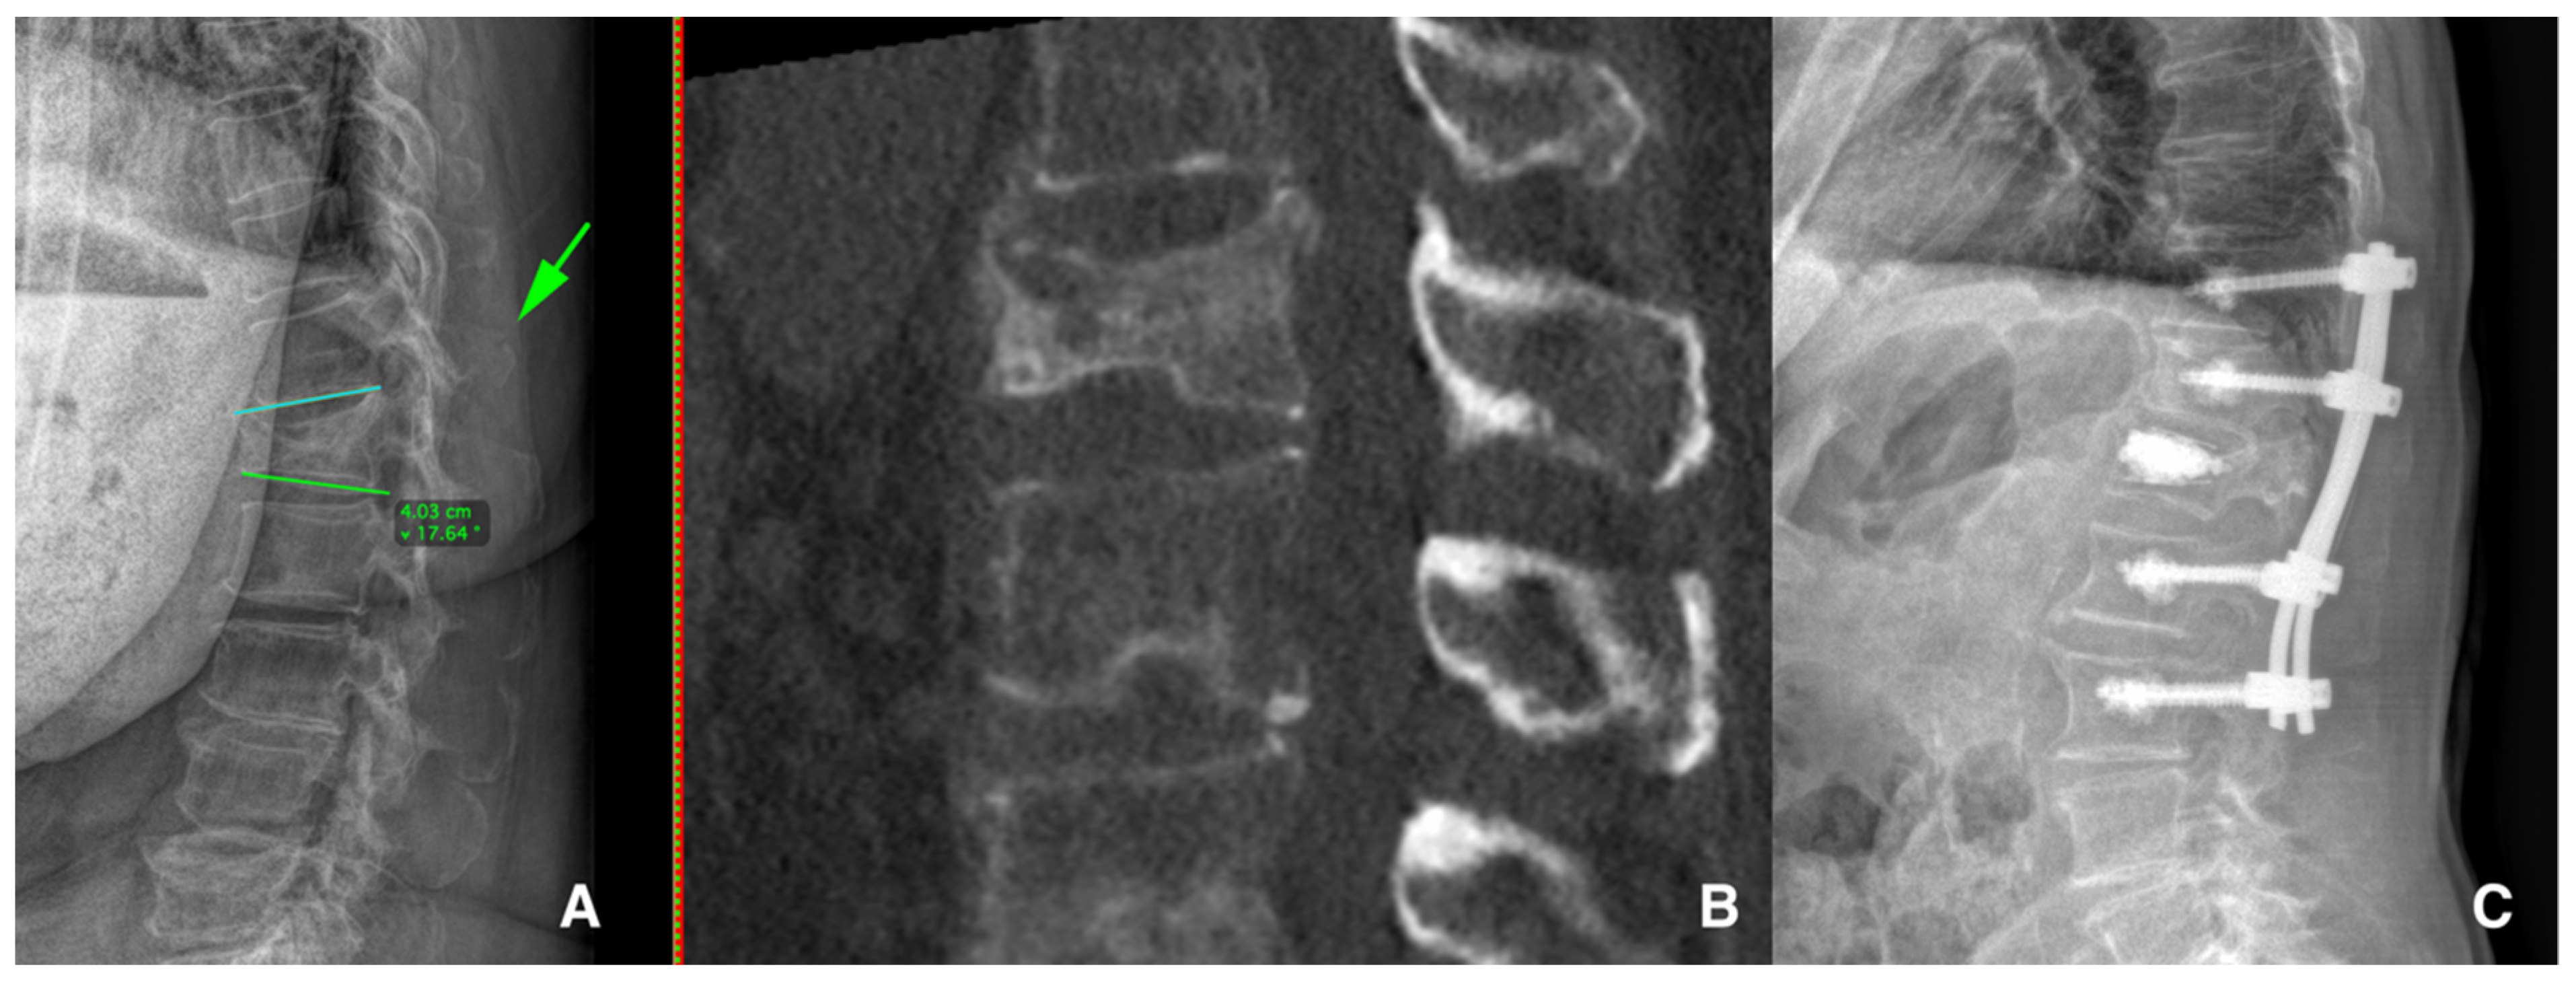

- Scheyerer, M.J.; Spiegl, U.J.A.; Grueninger, S.; Hartmann, F.; Katscher, S.; Osterhoff, G.; Perl, M.; Pumberger, M.; Schmeiser, G.; Ullrich, B.W.; et al. Risk factors for failure in conservatively treated osteoporotic vertebral fractures: A systematic review. Glob. Spine J. 2022, 12, 289–297. [Google Scholar] [CrossRef]

- Zhang, J.N.; He, X.; Fan, Y.; Du, J.P.; Hao, D.J. Risk factors for conservative treatment failure in acute osteoporotic vertebral compression fractures (OVCFs). Arch. Osteoporos. 2019, 14, 24. [Google Scholar] [CrossRef]

- Lee, H.M.; Park, S.Y.; Lee, S.H.; Suh, S.W.; Hong, J.Y. Comparative analysis of clinical outcomes in patients with osteoporotic vertebral compression fractures (OVCFs): Conservative treatment versus balloon kyphoplasty. Spine J. 2012, 12, 998–1005. [Google Scholar] [CrossRef]

- Park, H.Y.; Ahn, J.H.; Ha, K.Y.; Kim, Y.H.; Kim, S.I.; Min, H.K.; Oh, I.S.; Seo, J.Y.; Park, S.H. Clinical and radiologic features of osteoporotic spine fracture with delayed neurologic compromises. World Neurosurg. 2018, 120, E1295–E1300. [Google Scholar] [CrossRef] [PubMed]

- Hayashi, T.; Maeda, T.; Masuda, M.; Ueta, T.; Shiba, K. Morphology of the injured posterior wall causing spinal canal en-croachment in osteoporotic vertebral fractures. Spine J. 2016, 16, 946–950. [Google Scholar] [CrossRef]

| Park H.Y. et al. (2018) [31] Hayashi T. et al. (2016) [32] | Vertebral collapse and spinal canal compromise and/or delayed neurological deficit | Posterior wall involvement, initial height loss, midportion-type fractures, swelled-front-type fractures, complex fracture morphology, intravertebral cleft development, fracture instability, fractures at the thoracolumbar junction and specific MRI changes |

| Goldstein S. et al. (2016) [34] Ha K.Y. et al. (2013) [35] Patil S. et al. (2014) [36] | Progressive vertebral collapse or progressive kyphotic deformity | Location at thoracolumbar junction, midportion-type fractures, intervertebral cleft development, specific fracture types, posterior wall fractures, superior endplate involvement, anterior wall fractures and previous adjacent level fractures |